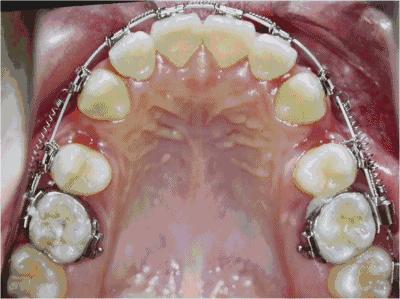

其次是成人,矫正完取下矫治器后,牙齿在新的位置上还不算是稳定,这时往往还需要戴上保持器来保持牙齿在牙槽骨上新位置的稳定,直到牙槽骨的改建完成。

由于牙齿畸形的因素、性质及严重程度不同,有的人可能只需佩戴1~2年的保持器,有的人则可能要永久佩戴保持器。因此上述所说的成年人,如果后期出现矫正反弹,最大的原因就是保持器佩戴时长的问题造成的。(ps:毕竟明星的工作也是很忙的,忘记戴保持器也很正常)